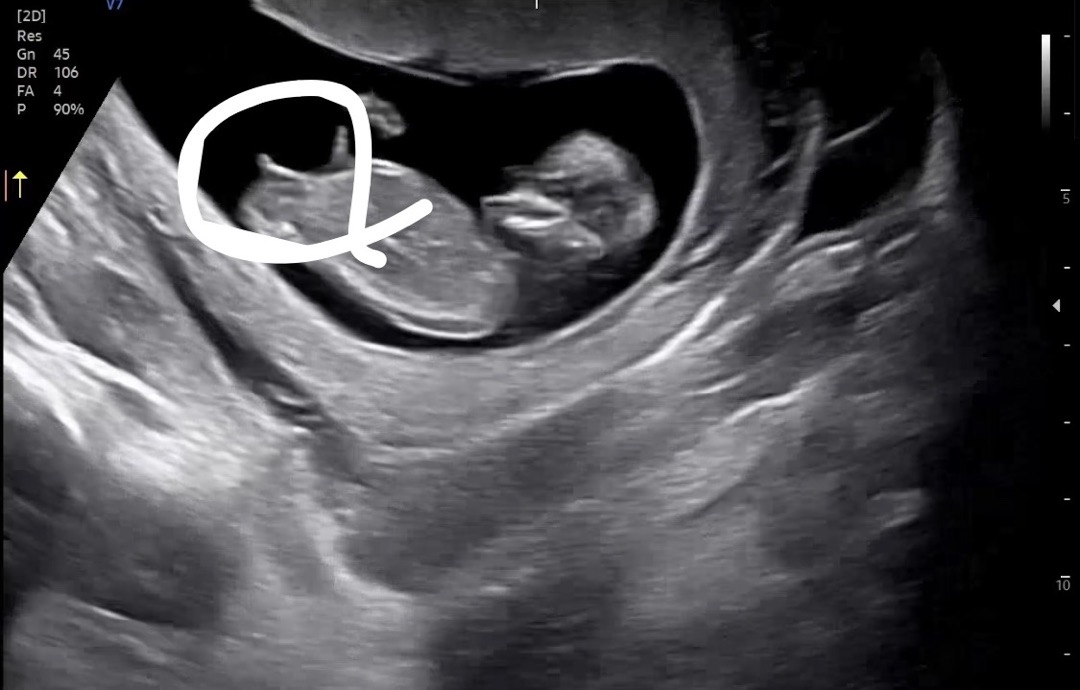

12주차 각도법 봐주실래요👶🏻

12주 0일차 입니다 혹시 각도법 봐주실 수 있을까요?? 댓글에 추가 사진 올렸습니다